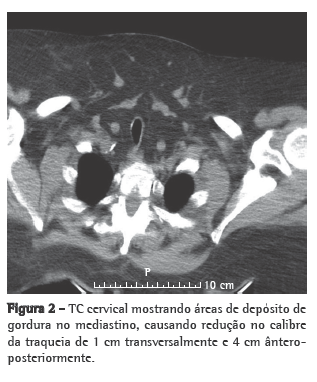

As condições clínicas do paciente melhoraram progressivamente, com a subsequente redução das pressões BiPAP e do uso do ventilador, que foi interrompido no 6º dia de internação em virtude do aparecimento de ulcerações faciais causadas pela máscara nasal. Durante a primeira noite sem ventilação não-invasiva, houve longos períodos de dessaturação de oxigênio (SpO2 < 88%) e ronco. O paciente foi então submetido à TC cervicofacial (Figuras 1 e 2) e a um estudo cardiorrespiratório do sono.

O estudo do sono levou aproximadamente 8 h, revelando grave apneia obstrutiva do sono (índice de apneia-hipopneia: 37 eventos/h; índice de apneias obstrutivas: 29 eventos/h; mediana de saturação periférica de oxigênio durante o sono: 88%; índice de dessaturação de oxigênio: 51%/h; e SpO2 mínima: 51%). A TC revelou várias áreas de depósitos de gordura no mediastino, causando uma redução no calibre da traqueia de 1 cm transversalmente e 4 cm ântero-posteriormente. A titulação da continuous positive airway pressure (CPAP, pressão positiva contínua nas vias aéreas) foi realizada na segunda noite, e o paciente recebeu alta. Em casa, o paciente permaneceu em ventilação BiPAP (EPAP: 8 cmH2O; IPAP: 16 cmH2O), realizada através de almofadas nasais (Figura 3).